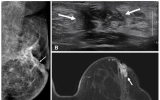

사회 뉴시스2025. 11.05[나이스데이] 국내 연구진이 수술 전 MRI(자기공명영상)가 50세 이하 유방암 환자의 재발 예방에 효과적이라는 사실을 규명했다. 특히 예후가 나쁘고 재발률이 높은 '호르몬 수용체 음성 유방암'은 재발 위험이 60% 이상 낮아지는 것으로 나타났다. 이는 젊은 유방암 환자의 맞춤형 치료 가능성을 높이고, 유방 MRI 기반의 정교한 치료 계획을 수립하는 중요한 가이드라인이 될 것으로 기대된다. 서울대병원은 하수민·연희라 영상의학과 교수, 김홍규 유방내분비외과 교수팀이 2011년부터 2017년까지 수술을 받은 50세 미만…